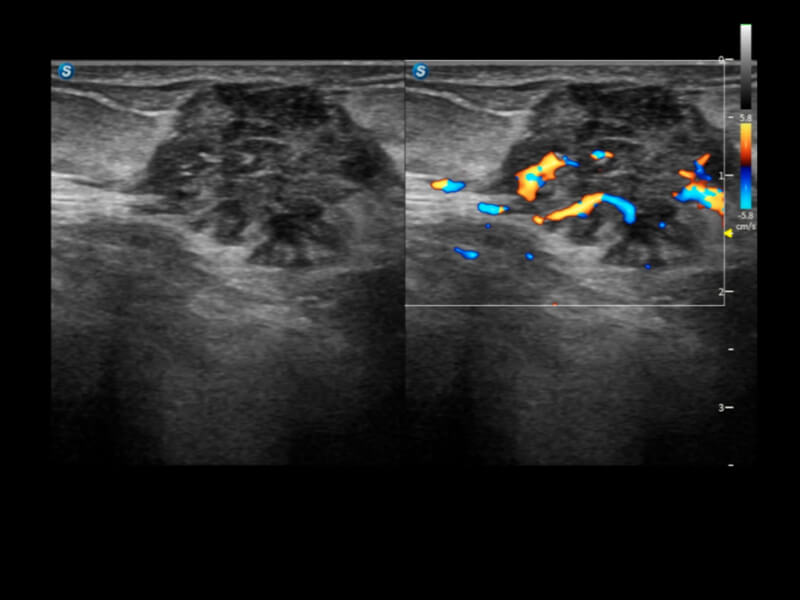

丰富的血流动力学检测技术,可在不同医疗场景中高效捕捉血流信号,助力临床诊疗。

在传统血流的基础上优化扫查和算法策略,能够更好的抑制组织信息,提炼红细胞运动信息,得到更高帧频,高灵敏度和分辨率的血流信号,还原更真实的血流动力学。

通过光照模型,使二维血流显示出立体的效果,增加血流的敏感性、成束性,减少外溢。可以和其他不同的血流技术联合使用,融合不同技术的优势。轻松应对微小血管,增强血流的立体效果,提升视觉敏感性。

通过创新的Matrix E自适应滤波算法,能有效滤除软组织和噪声信号,最大限度保留超低速微细血流的信号;结合超长时间域算法,极大提升细微血流的敏感性和空间分辨率,更真实的反应组织、包块的血流灌注情况。